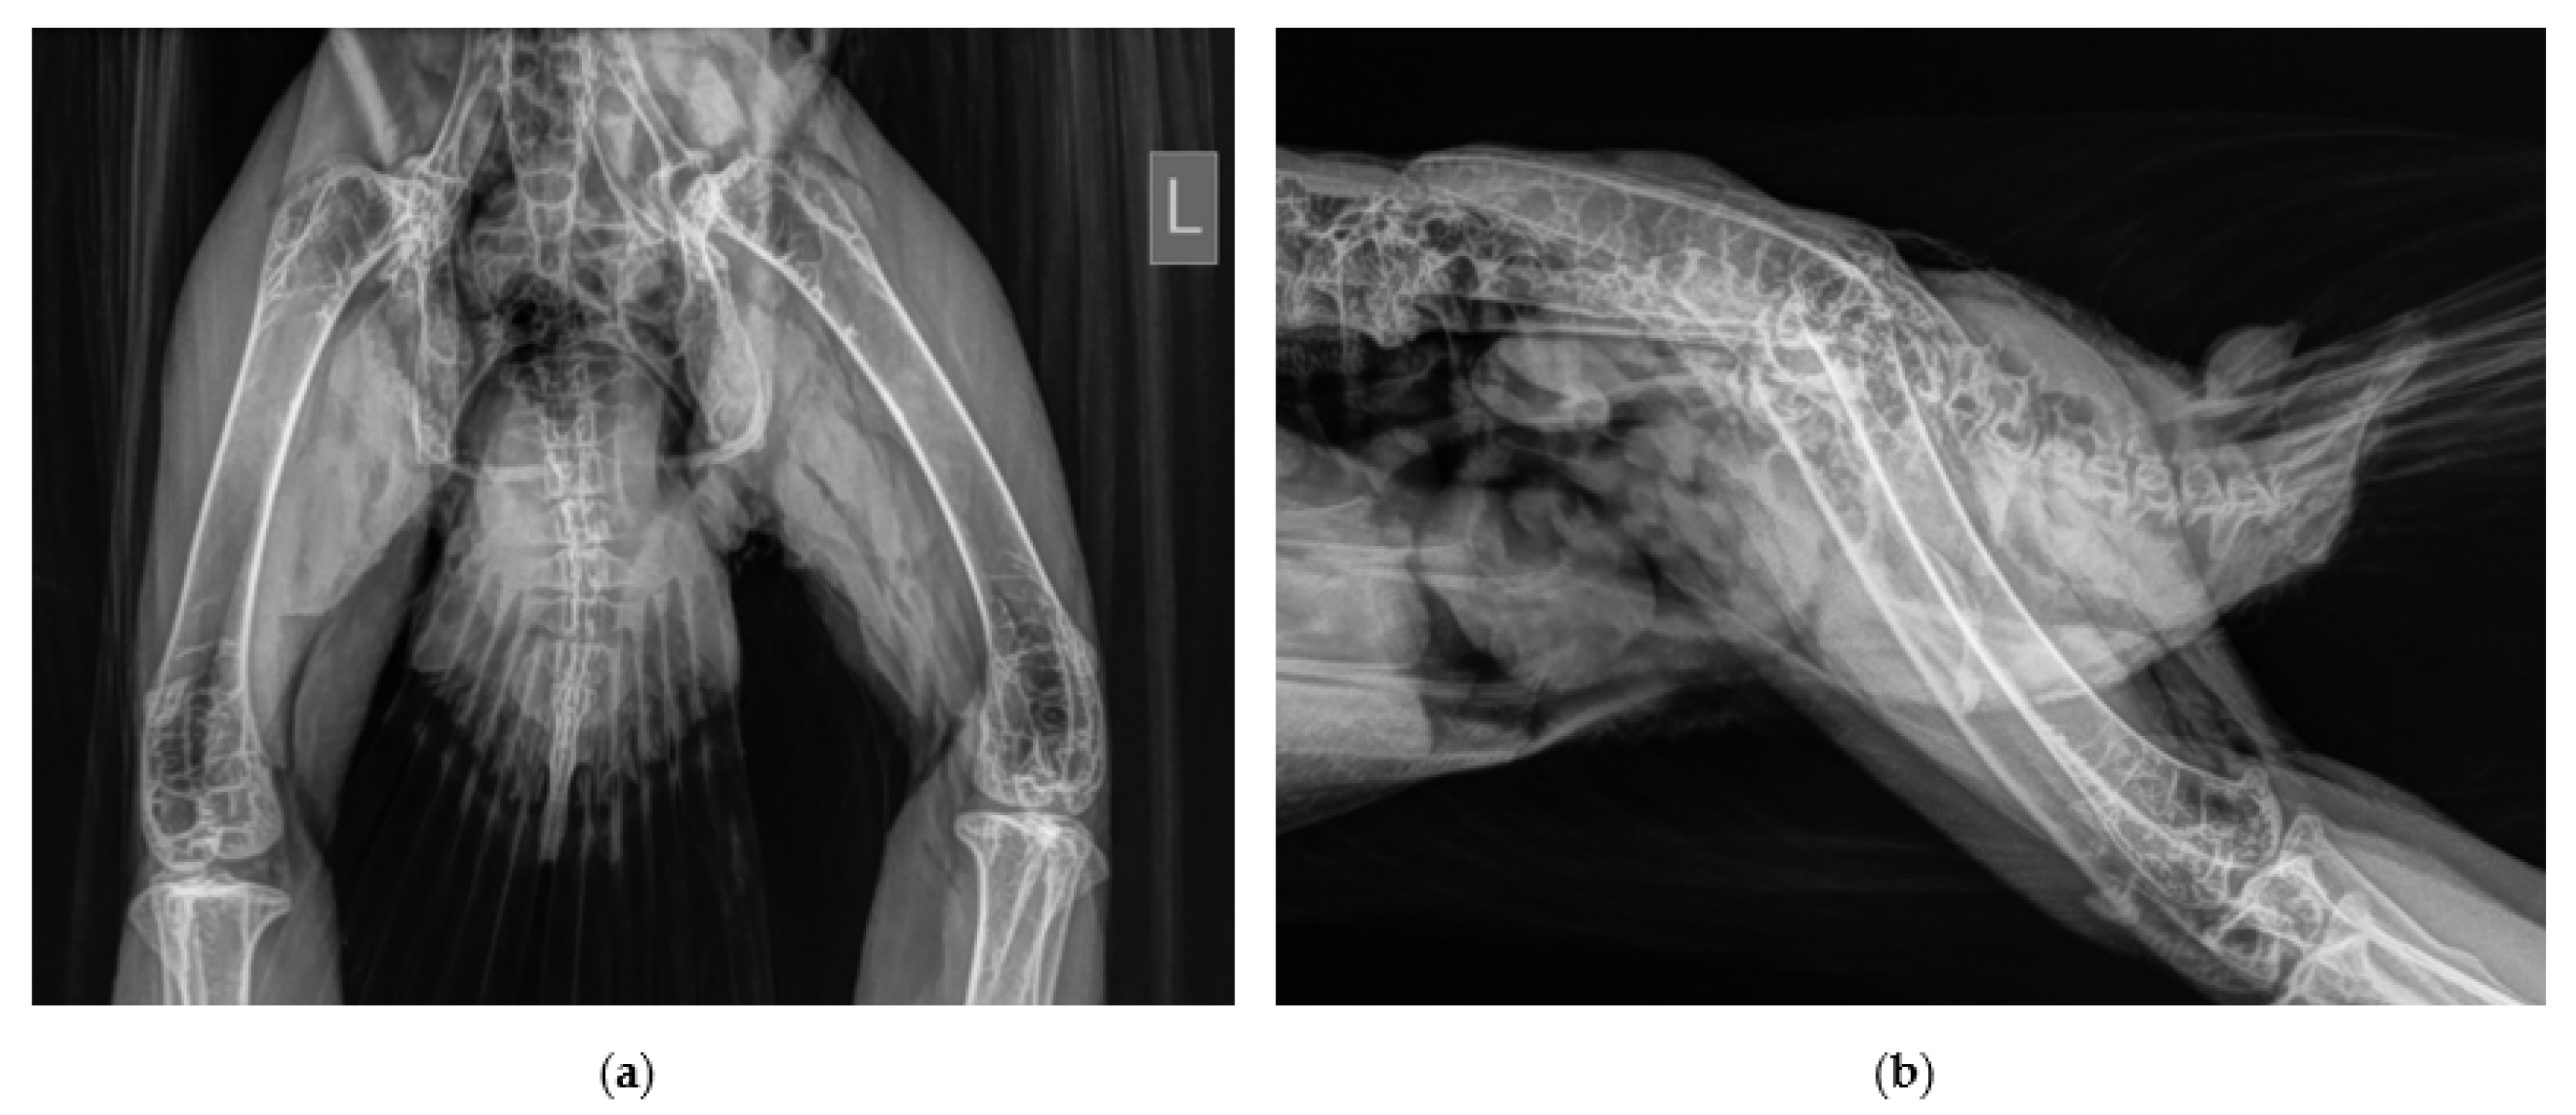

2.2. Surgical Procedure and Post-Surgery Management